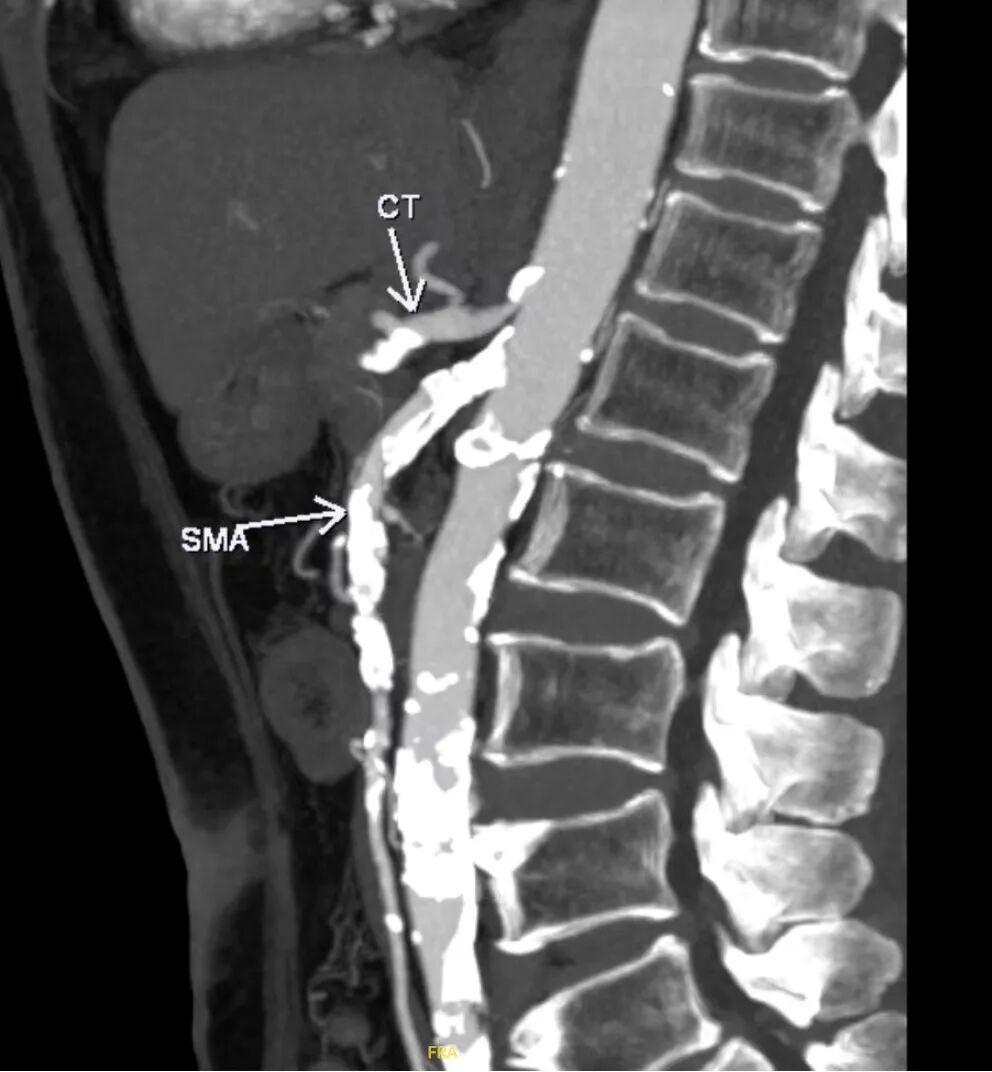

腹主动脉CTA:腹主动脉管壁见多发钙化、部分钙化斑块,管腔轻度狭窄。双肾动脉起始处见钙化斑块,管腔轻度狭窄,以远管腔显影可;腹腔干起始部可见部分钙化斑块,管腔狭窄程度约70%。脾动脉管壁见弥漫钙化斑块,管腔中-重度狭窄。肠系膜上动脉起始部见高密度支架,支架形态欠佳,局部腔内见多发钙化,管腔狭窄程度约70%。肠系膜下动脉见部分钙化斑块,管腔中度狭窄。

矢状位 MAP

肠系膜上动脉

CTA重建

肠系膜上动脉开口